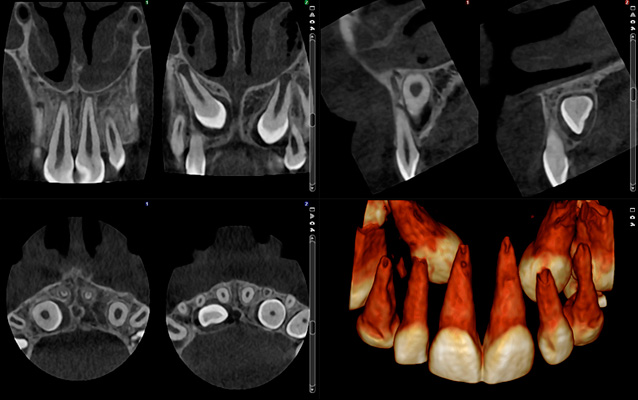

Planmeca ProMax 3D Classic - FOV Ø 40 x 50 mm. - Rozmiar Woksela 150 µm - Efektywna dawka dla pacjenta 14.4 µSv

Obraz Ultra niska dawka – Przypadek ortodontyczny

Planmeca ProMax 3D - FOV Ø 85 x 50 mm. - Rozmiar Woksela 400 µm - Efektywna dawka dla pacjenta 7.9 µSv

Planmeca ProMax 3D - FOV Ø 85 x 50 mm. - Rozmiar Woksela 400 µm - Efektywna dawka dla pacjenta 4.0 µSv